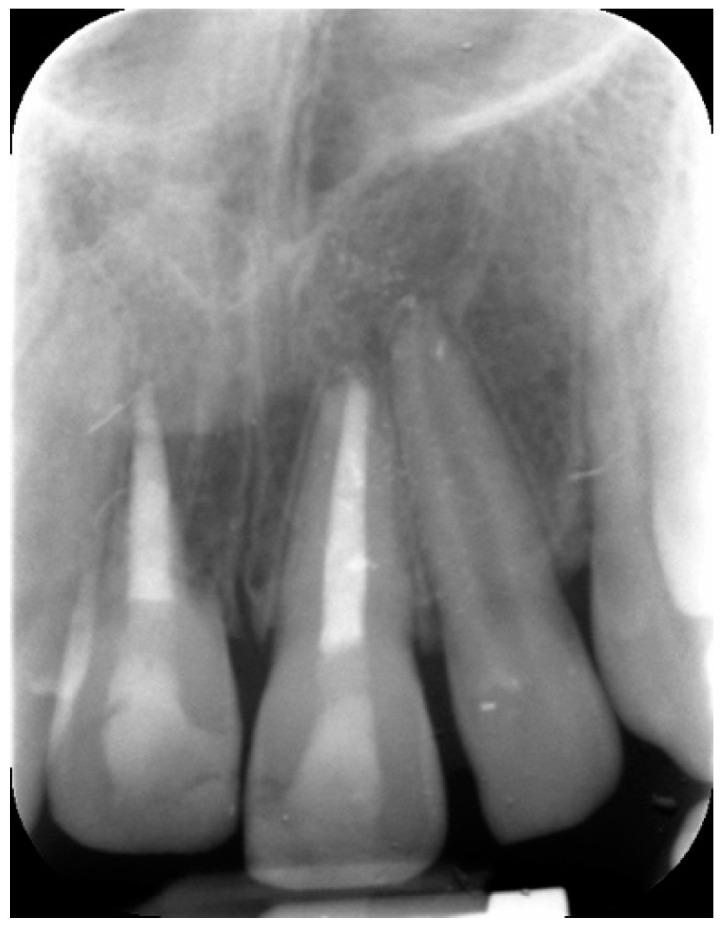

: Avulsion and reimplantation of permanent teeth represent a major challenge in terms of treatment and long-term prognosis. The present study reported clinical management of external root resorption of an avulsed and reimplanted maxillary central incisor. : A 9-year-old boy reported an uncomplicated crown fracture and avulsion of tooth 11 and complicated crown fracture of tooth 21 due to trauma. Reimplantation of element 11 was obtained within 30 min post-trauma and 3 days after both elements were diagnosed with necrotic pulp. In addition, tooth 11 showed early external root resorption. Both elements underwent endodontic treatment and root closure with apical plug using calcium-silicate-based cement. At 6-month follow-up root resorption appeared to be arrested. Twenty-four months after trauma the clinical results were stable, although signs and symptoms of ankylosis were observed. : An immediate endodontic approach and use of calcium-silicate-based cement seemed to contrast the progression of root resorption of an avulsed and reimplanted central incisor after 24 months of follow-up.

恒牙的脱位与再植在治疗及长期预后方面是一项重大挑战。本研究报告了一例上颌中切牙脱位再植后牙根外吸收的临床处理情况。:一名9岁男孩因外伤导致11号牙冠折未伴复杂情况及脱位,21号牙冠折伴复杂情况。外伤后30分钟内完成1号牙再植,两颗牙均被诊断为牙髓坏死3天后进行处理。此外,11号牙出现早期牙根外吸收。两颗牙均接受了根管治疗,并使用硅酸钙基水门汀进行根尖封闭以促进牙根闭合。6个月随访时,牙根吸收似乎停止。外伤24个月后临床结果稳定,尽管观察到了牙齿粘连的体征和症状。:经过24个月的随访,立即进行根管治疗并使用硅酸钙基水门汀似乎抑制了脱位再植中切牙牙根吸收的进展。